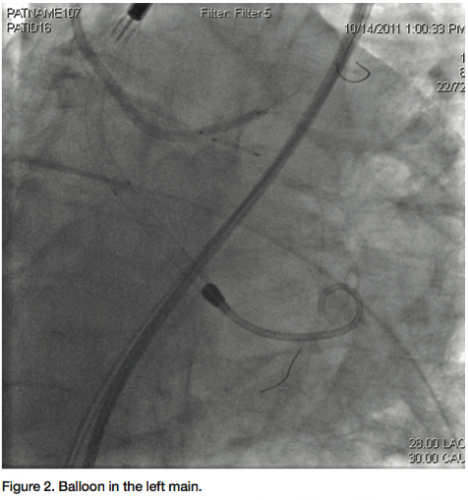

a Judkins left 3.5 guiding catheter was used to engage the left main. Two 0.014” angioplasty wires were introduced; one into the LAD, and one into the distal Cx. A 3.0 x 12 mm balloon was placed in the ostium of the Cx, and a diagnostic angiogram was obtained (Figure 1). Subsequently, a 2.5 mm balloon was placed from the left main into the LAD. A 3.5 x 8 mm bare-metal stent was placed in the proximal Cx. The 2.5 mm balloon was inflated to 10 atmospheres, protecting the left main and proximal LAD from plaque shifting during deployment of the Cx stent (Figure 2). The stent in the Cx was then withdrawn until it indented the left main balloon. The balloon in the left main was inflated for nearly a minute during this process, and the patient was completely asymptomatic. Systolic blood pressure did drop from about 130 mmHg to about 90 mmHg, but diastolic pressure was maintained due to support from the Impella 2.5 circulatory support device. Both balloons were then simultaneously inflated for about 25 seconds (Figure 3). The patient transiently developed global ST elevation and systolic hypotension, but remained asymptomatic. After both balloons were deflated, final images revealed excellent coverage of the ostial Cx lesion, with no significant compromise of the left main and LAD. Intravascular ultrasound (IVUS) analysis after stent deployment revealed a cross sectional area of 6.3 mm2 in the ostium of the LAD, with excellent visualization of the Cx stent in the ostium. At the conclusion of the procedure, the Impella 2.5 circulatory device was weaned off in the cath lab, and the 13 French sheath was removed, with the pre-placed sutures securing hemostasis. The right femoral sheath was also secured using a single Perclose Proglide device. The patient was uneventfully discharged home the following morning.